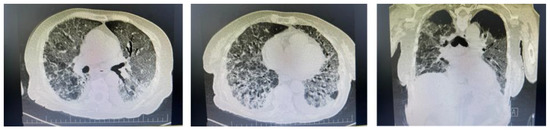

2. Clinical Experience—Case Report